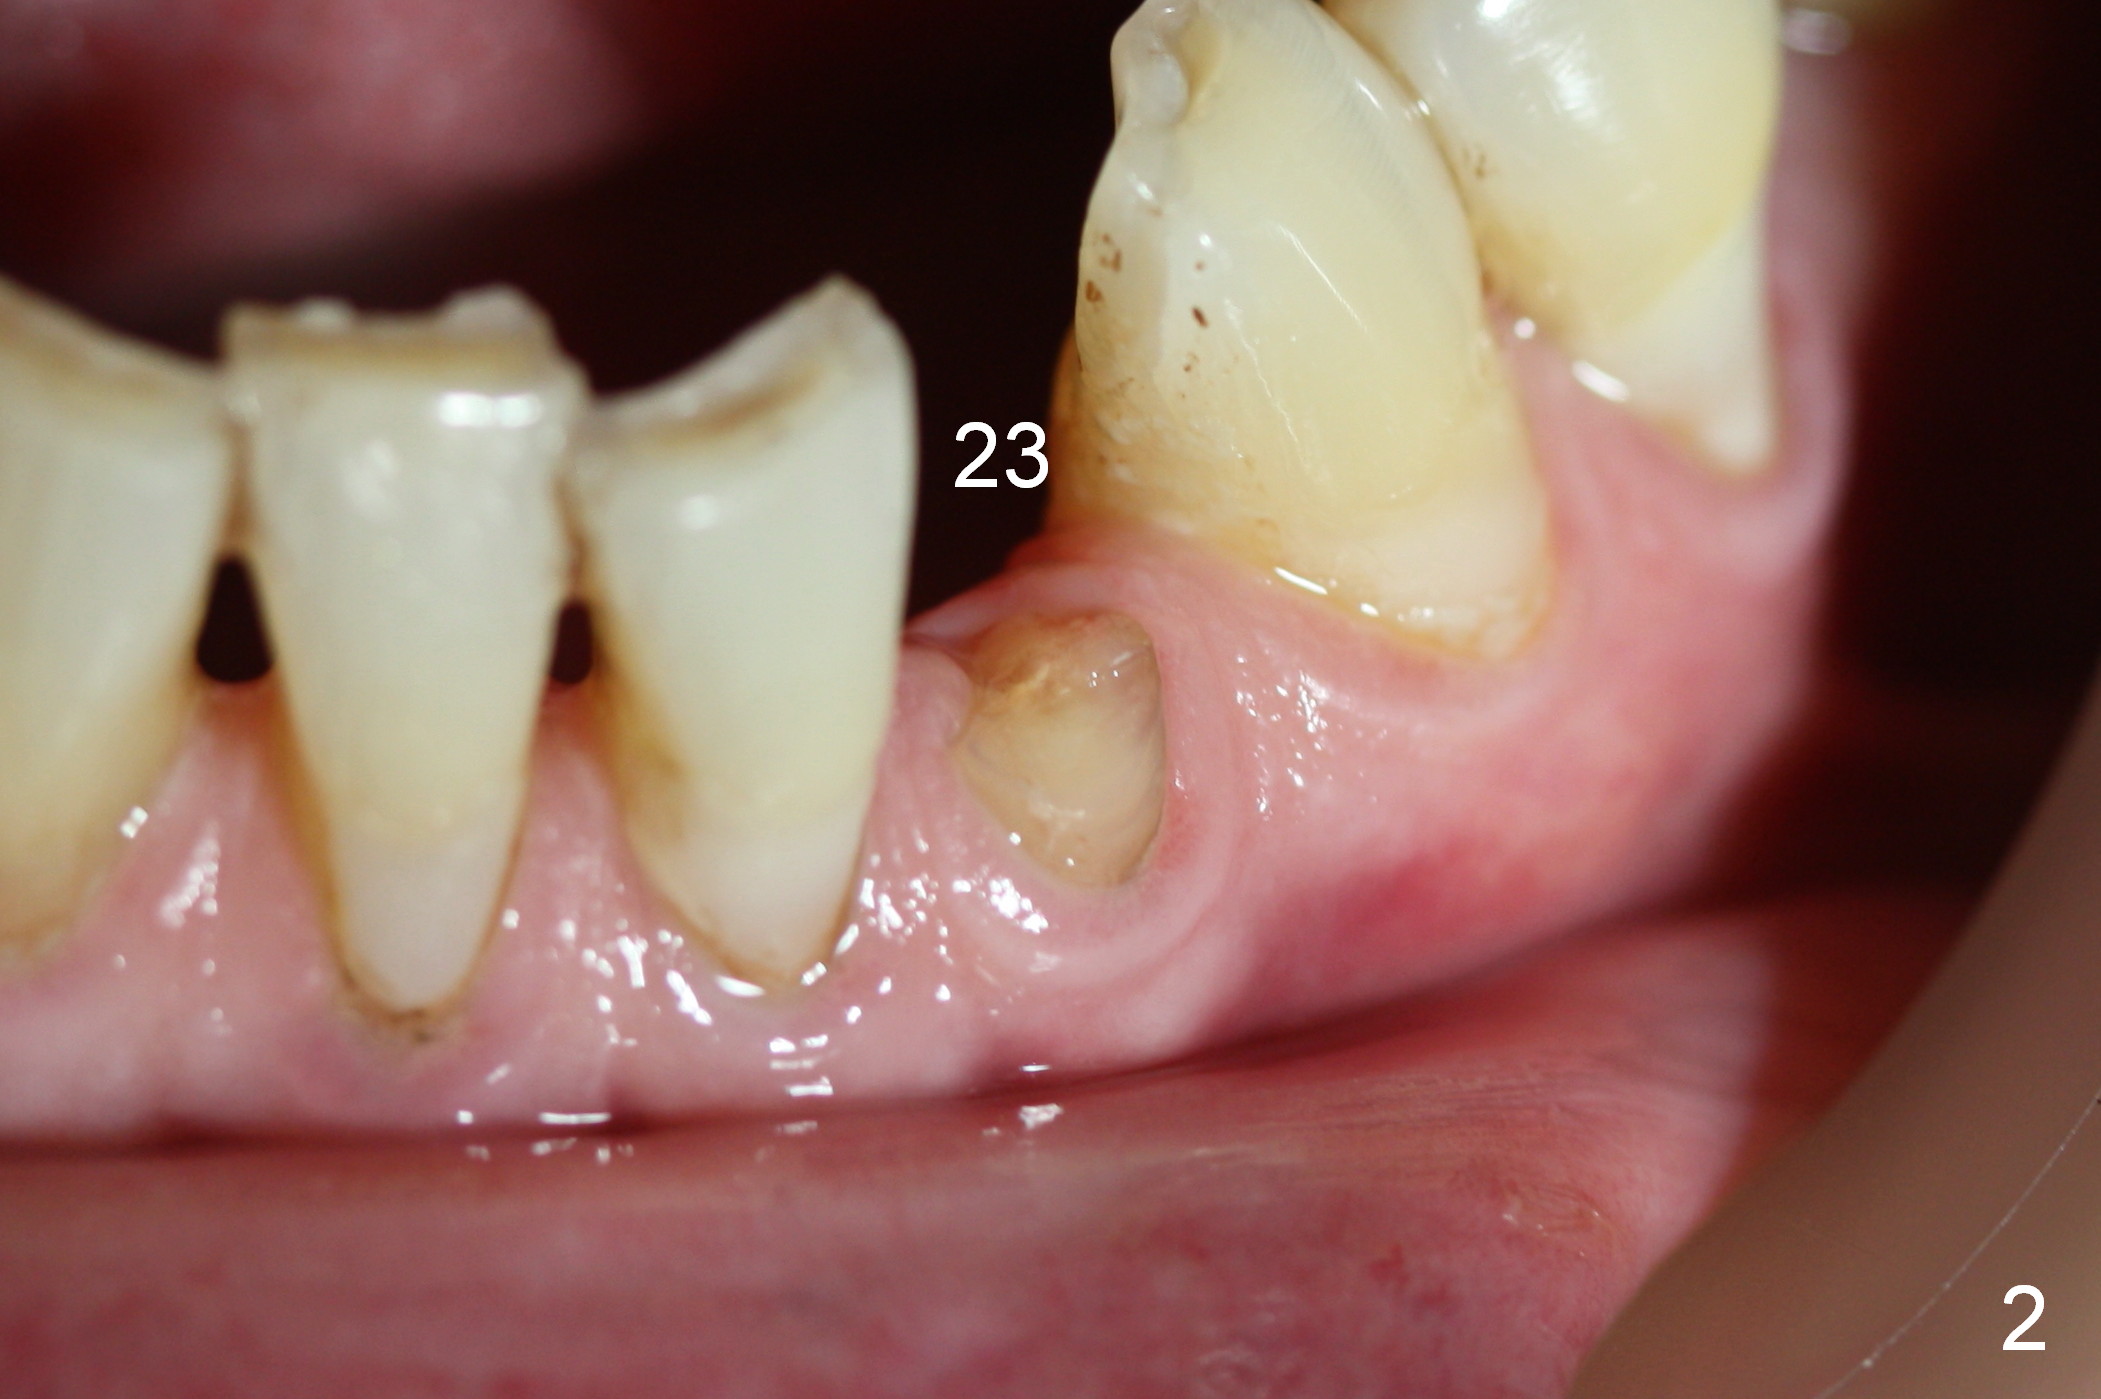

A 74-year-old man has several missing teeth (Fig.1). His 1st goal is to replace the lower left lateral incisor (Fig.2). The residual root has an apical lesion (Fig.3 *). To describe intraop findings, a CT image of a different patient is used (Fig.4 coronal section; B: buccal; L: lingual). After extraction, the buccal plate is found to be thin and low (Fig.5 arrowheads). A 1.5 mm pilot drill (Fig.6 red line) is used to initiate osteotomy in the lingual plate of the socket. Once the drill penetrates the lingual plate, the trajectory changes and the depth is 17 mm from the gingival margin (Fig.7). A PA is taken (Fig.8); it appears that the osteotomy can be extended more apically. When the pilot drill extends to 20 mm, there is sudden empty feeling. The lingual plate has perforated (Fig.9). A new osteotomy is established buccally (Fig.10 pink). To avoid buccal plate perforation, especially in the buccal undercut area (>), the coronal end of the drill has to be tilted buccally (<--). An angled abutment (3x20 mm, 15°) is placed (Fig.11,12). The abutment is modified (Fig.13,14) to accommodate an immediate provisional (Fig.15,16 P). Perio dressing is to be applied to prevent the bone graft from getting dislodged buccally (Fig.15). The dressing is in place 7 days postop (Fig.17).